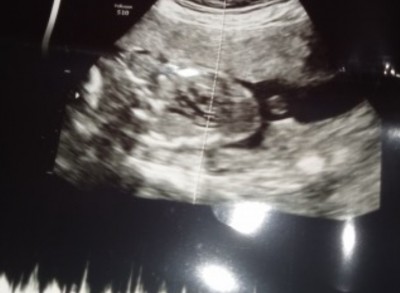

Kızlar nedir bebeğimin cinsiyeti anlayanlar yorum yapabilirmi

Gebelik haftası 23 hafta 4 gün

Resmen kız bebek bacak arası resmini vermiş sağlıkla gelsin

Cnm kız bu cnku çıkıntısı yok yani kaçıncı bebegin